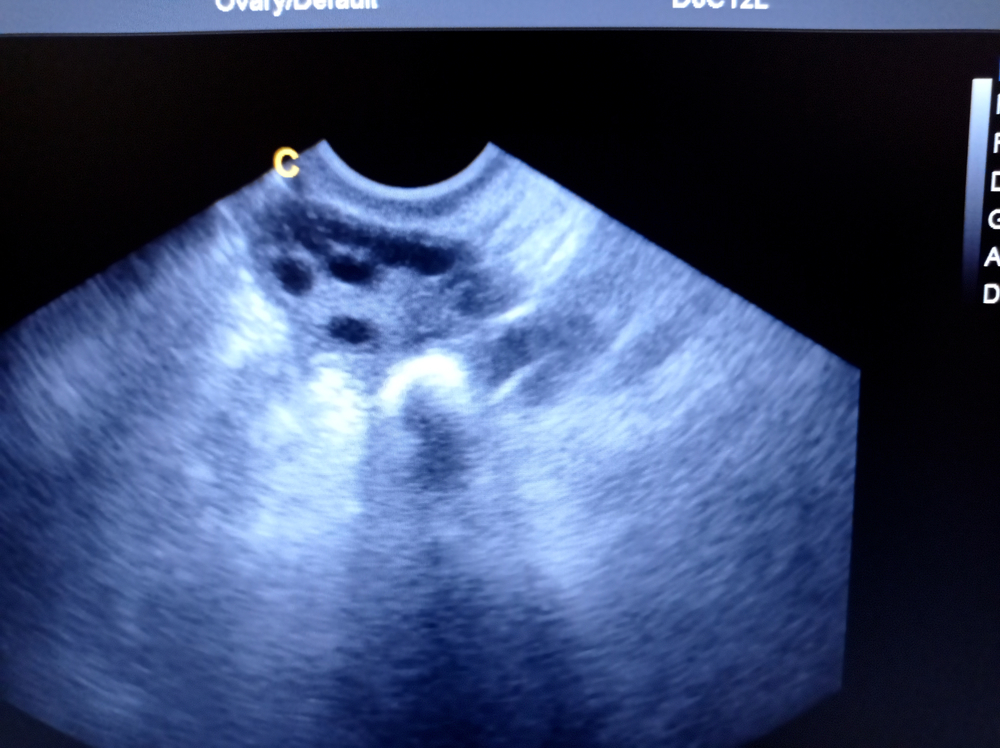

Особенность диагностики в том, что в обычном состоянии трубы почти не видны: они полые, тонкие, «спавшиеся», и на стандартном УЗИ их внутренняя часть в норме не визуализируется. Поэтому при УЗИ проходимости маточных труб используют заполнение раствором или контрастом: жидкость заполняет полость и делает ход труб заметнее на экране.

- Затем через шейку матки аккуратно вводит тонкий катетер небольшого диаметра (обычно это мягкий проводник). Посредством катетера вводят физиологический раствор или жидкость контрастного типа– она заполняет полость матки и дальше проходит в трубы. На экране врач видит процесс заполнения: как контраст движется по трубам и выходит ли в брюшную полость.

В заключении указывают, что удалось оценить и какие результаты получены. На практике ультразвуковая диагностика маточных труб отвечает на два главных вопроса: есть ли проход и на каком участке может быть препятствие.

Что показывает УЗИ в норме:

- контраст или раствор свободно заполняет полость матки и затем проходит по обеим трубам;

- видно поступление жидкости в брюшную полость с обеих сторон (признак проходимости);

- полость матки без выраженного патологического «рельефа», эндометрий соответствует дню цикла;

- нет признаков выраженного воспаления, грубых деформаций стенки.

Как описывают патологию:

- полная непроходимость: контраст не проходит дальше определенной точки, выхода в брюшную полость нет; труба может растягиваться при заполнении;

- частичная непроходимость: жидкость проходит с задержкой, выход минимальный, возможно сужение просвета;

- спаечный процесс: врач указывает признаки спаек (внутри просвета или снаружи), отмечает количество и предполагаемую локализацию;

- аномалии строения: врожденные варианты формы, перегибы, особенности положения, которые могут мешать прохождению;

- сопутствующие находки в матке: полипы, синехии, изменения слизистой, которые тоже важны для зачатия;

- спазм: иногда нарушение проходимости может быть функциональным; в таких случаях врач отмечает, что результат может требовать уточнения другими методами.